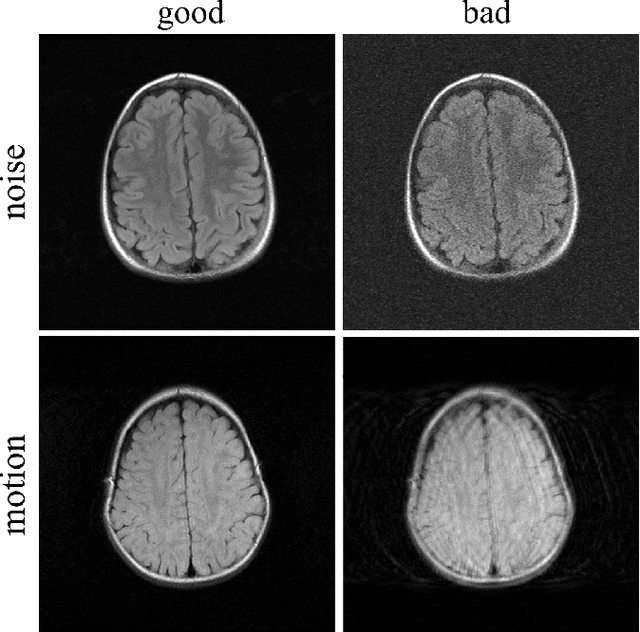

Abstract:In clinical practice MR images are often first seen by radiologists long after the scan. If image quality is inadequate either patients have to return for an additional scan, or a suboptimal interpretation is rendered. An automatic image quality assessment (IQA) would enable real-time remediation. Existing IQA works for MRI give only a general quality score, agnostic to the cause of and solution to low-quality scans. Furthermore, radiologists' image quality requirements vary with the scan type and diagnostic task. Therefore, the same score may have different implications for different scans. We propose a framework with multi-task CNN model trained with calibrated labels and inferenced with image rulers. Labels calibrated by human inputs follow a well-defined and efficient labeling task. Image rulers address varying quality standards and provide a concrete way of interpreting raw scores from the CNN. The model supports assessments of two of the most common artifacts in MRI: noise and motion. It achieves accuracies of around 90%, 6% better than the best previous method examined, and 3% better than human experts on noise assessment. Our experiments show that label calibration, image rulers, and multi-task training improve the model's performance and generalizability.